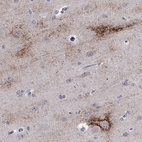

Immunohistochemical staining of human cerebral cortex shows strong membranous positivity in neurons.